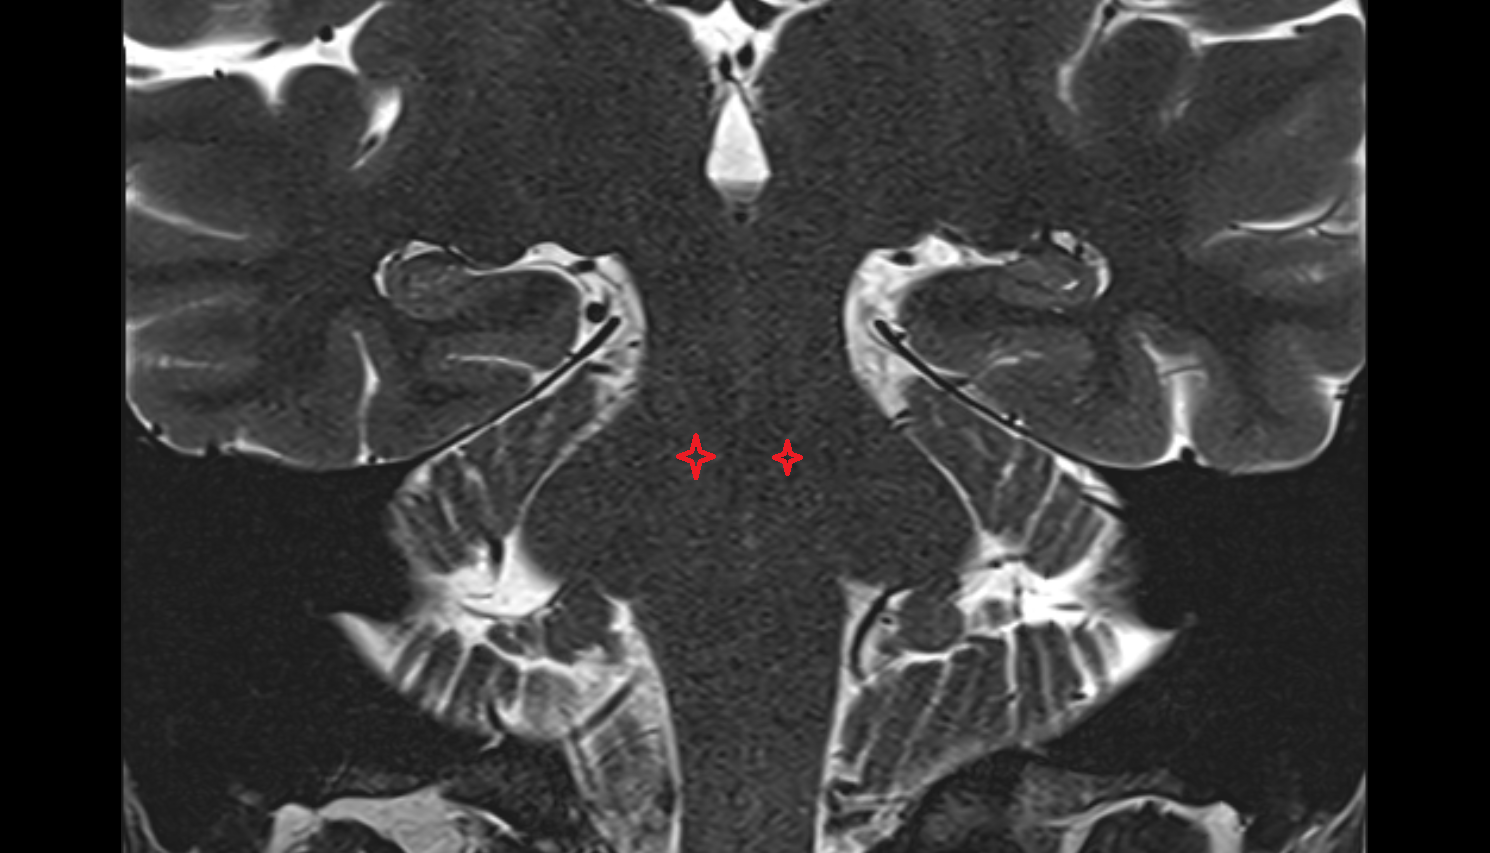

- Flocculus

- Crus I of ansiform lobule of cerebellum

- Crus II of ansiform lobule of cerebellum

- Paramedian lobule (HVII) of cerebellum

- Simple lobule (HVI) of cerebellum

- Anterior quadrangular lobule (HV) of cerebellum

- Anterior quadrangular lobule (HlV) of cerebellum

- Biventral lobule (HVIII) of cerebellum

- Central lobule (II & III) of Cerebellum

- Culmen (IV, V) of Cerebellum

- Declive (VI) of Cerebellum

- Folium (VII) of Cerebellum

- Tuber of vermis (VII)

- Pyramid of vermis (VIII)

- Uvula of vermis (IX)

- Nodule of vermis (X)

- Cerebellar tonsil (H IX)